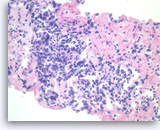

Plasma cell neoplasm,

Pancreas FNA, Direct Smear.

The aspirates show dispersed single cells with a prominent plasmacytoid appearance. The tumor cells vary slightly in size. Rare mitoses are seen.

20X

Plasma cell neoplasm,

Pancreas FNA, Direct Smear.

The aspirates show dispersed single cells with a prominent plasmacytoid appearance. The tumor cells vary slightly in size. Rare mitoses are seen.

20X

Plasma cell neoplasm,

Pancreas FNA, Direct Smear.

The tumor cells show perinuclear hof (clearing). Binucleated tumor cells are occasionally seen. Scattered lymphoglandular bodies are seen in the background.

40X

Plasma cell neoplasm,

Pancreas FNA, Direct Smear.

The tumor cells show perinuclear hof (clearing). Binucleated tumor cells are occasionally seen. Scattered lymphoglandular bodies are seen in the background.

40X

Plasma cell neoplasm,

Pancreas FNA, Direct Smear.

The tumor cells have eccentrically located round nuclei with clumped chromatin and small nucleoli.

40X

Plasma cell neoplasm,

Pancreas FNA, Direct Smear.

The tumor cells have eccentrically located round nuclei with clumped chromatin and small nucleoli.

40X